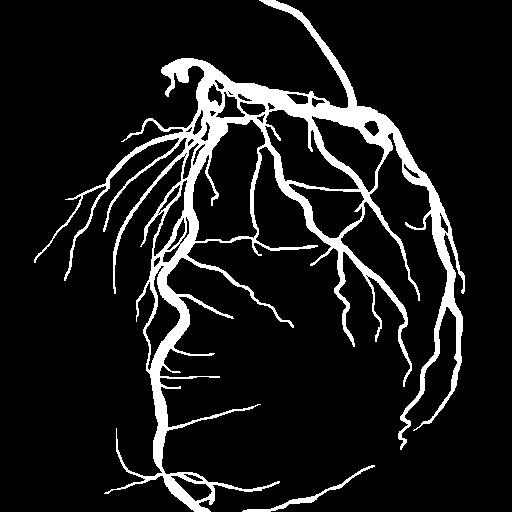

| Image | Ground truth | Video frame | Ground truth | Video frame | Ground truth |

| XCAD [33] | CADICA [19] | Our XACV dataset | |||

4.1 XACV Dataset

We collect 111 complete records of coronary artery X-ray videos, encompassing the injection, flow through the blood vessels around the heart, and dissipation of the contrast agent. Subsequently, we establish the XACV (X-ray Angiography Coronary Video) dataset. Each video consists of varying numbers of high-resolution coronary artery X-ray images. We invite experienced radiologists to annotate the vascular regions, focusing on one or two frames where the contrast agent is most prominent in each video. The XCAD dataset contains only a single image, and the CADICA video dataset does not provide corresponding ground truth. Therefore, in the following experiments, we conduct all the analyses on our collected XACV dataset and the corresponding GT for each sequence. In Figure 5, we show that compared to other publicly available datasets, XCAD [33] and CADICA [19], our dataset exhibits finer annotations in the vascular regions, providing an advantage for future related tasks. The development and use of our dataset have been approved by our institution’s IRB.